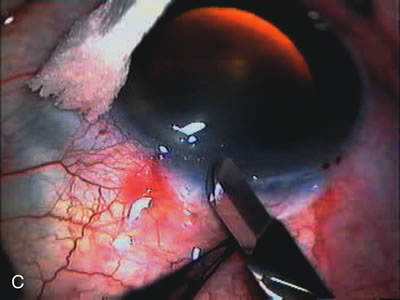

PHACOVISCOCANALOSTOMY AND PHACO/DEEP SCLERECTOMY FOR UNCONTROLLED GLAUCOMA AND SYMPTOMATIC CATARACT

Nonpenetrating procedures as they exist today generally decrease postoperative complications but do not reduce IOP as successfully as trabeculectomy.140 The success rate also appears to be highly dependent on race, length of topical antiglaucoma therapy, and prior ocular surgery.141,142 Deep sclerectomy combined with phacoemulsification results in an IOP reduction similar to phacotrabeculectomy at one year with comparable visual outcome.143 Phacoviscocanalostomy lowers IOP by approximately 33%144 through either a one- or two-site approach145 (Fig. 4). Nonpenetrating procedures are in evolution, and their place in long-term glaucoma care is still unclear.

Fig. 4. Viscocanalostomy with deep sclerectomy and phacoemulsification. Nonpenetrating filtration procedures (NPFS) may be combined with phacoemulsification. Patients with mild disc damage and a history of limited topical drug therapy are the best candidates. Patients who require an IOP in the low teens are not good candidates for NPFS. By definition, NPFS is designed to lower IOP without penetrating into the anterior chamber, thereby avoiding the complications associated with trabeculectomy. Viscocanalostomy is intended to allow aqueous to percolate through a trabeculodescemetic membrane into a subscleral cavern created by the deep sclerectomy. The aqueous diffuses from the cavern into the dilated ostia of Schlemm's canal and into the episcleral venous plexus. A. Fashion a uniform 300-micron superficial scleral flap 1 mm into clear cornea. B. Construct a second 600-micron deep flap that facilitates the unroofing of Schlemm's canal, seen as the darker area. C. Use viscoelastic to dilate the ostia of Schlemm's canal. The major problem with viscocanalostomy is the eventual closure of the ostium decreasing flow to the episcleral plexus. D. Dissect the deep flap anteriorly into clear cornea creating the trabeculodescemetic membrane. This membrane is clearly seen between the scleral spur and the bend of the deep flap. The integrity of this membrane ensures the nonpenetrating portion of the surgery. Another problem with NPFS is the eventual fibrosis of this initially transparent membrane requiring goniopuncture. E. Deep sclerectomy gets its name from removal of the deep flap. Removal of this flap creates the potential subscleral space for accumulation of aqueous before it enters Schlemm's canal and exits the episcleral venous plexus. After removal of the deep flap, the superficial flap is sutured into place and conjunctiva closed. Approximately half of these procedures develop a shallow bleb.